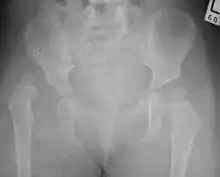

X-Ray Image showing hip dysplasia in a baby

Imaging

Hip dysplasia can be diagnosed by ultrasound[42] and projectional radiography ("X-ray").[43] Ultrasound imaging is generally preferred at up to 4 months due to limited ossification of the femoral head up until then, and is the most accurate method for imaging of the hip during the first few months after birth. However, in most instances, ultrasound screening should not be performed before 3 to 4 weeks of age because of the normal physiologic laxity.[44][notes 1] When universal with targeted ultrasound screening was compared, the former results in an insignificant reduction in the late diagnosis of hip dysplasia, which is why universal ultrasonographic screening of newborn infants is not recommended by the American Academy of Pediatrics.[11]

Despite the widespread use of ultrasound, pelvis X-ray is still frequently used to diagnose or monitor hip dysplasia or for assessing other congenital conditions or bone tumors.[45]

The most useful lines and angles that can be drawn in the pediatric pelvis assessing hip dysplasia are as follows:[45] Different measurements are used in adults.[45]